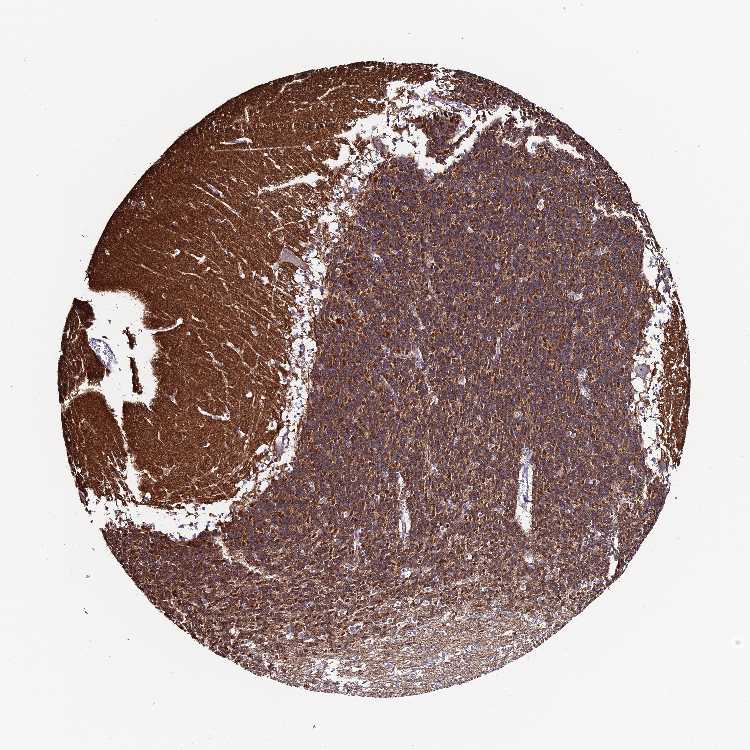

CEREBELLUM - Antibody stainingi

Antibody staining in the annotated cell types in the current human tissue is reported as not detected, low, medium, or high, based on conventional immunohistochemistry profiling in selected tissues. This score is based on the combination of the staining intensity and fraction of stained cells.

Each image is clickable and will lead to virtual microscopy that enables deeper exploration of all samples and also displays staining intensity scores, fraction scores and subcellular localization as well as patient and tissue information for each sample.

Antibody HPA024090

Purkinje cells Not detected

Cells in granular layer High

Cells in molecular layer Low